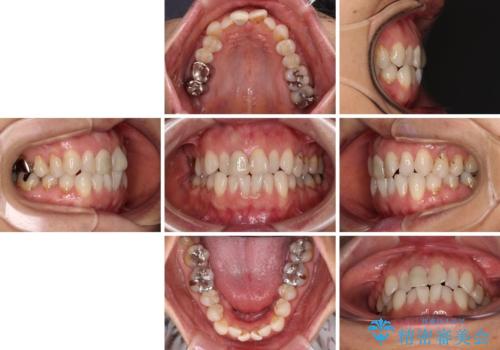

- 前歯のデコボコと口を開けたときに見える銀歯を気にして来院された患者様です。

ある程度デコボコが解消されれば大丈夫とのことで、インビザライン・モデレートパッケージを利用して歯列を整えて行くこととしました。

矯正治療後に銀歯をセラミッククラウンなどに置き換えていくと、どうしても後戻りを起こしてしまうため、矯正治療が概ね終了した時点で銀歯を全てセラミックとし、最後に仕上げでインビザラインにを用いて細かいデコボコを改善していくこととしました。